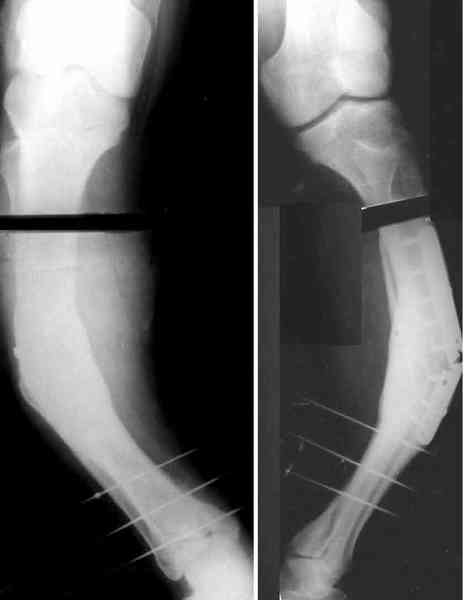

Удалили пластинку из двух доступов, винтик и спицу оставили. Сделан закрытый интрамедуллярный остеосинтез без рассверливания, прошло без

особенностей, стержень взял покороче, чтобы только до винта дошел. Снимок в приложении.

Для продолжения темы - несколько картинок.

Пациент 30 лет, лет пять назад оперирован по поводу перелома голени пластиной. Находясь на героине, нарушил режим, пошел, сломал и ногу и

пластину, но перелом сросся.

В приложении - внешний вид и рентген.

Пластинку и винты мне удалось разглядеть только на профильной проекции, точнее, трехчетвертной, судя по виду коленного сустава (правый снимок). На фасной - вообще не могу разобрать, где она :( Но, в конце концов, можно и не видя ее сказать, что уровень остеотомии может быть и другим, ниже или выше пластинки, придется только компенсировать смещение по ширине, которое появится при полном устранении угла не на вершине.